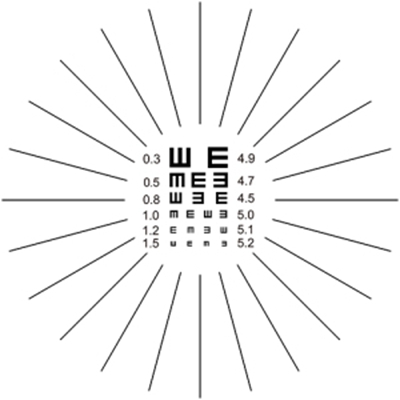

A:判斷自己有沒有散光,最簡單的方法是使用散光表來測試。散光表是一種簡單、方便的方法,但是它的準確度不是特別精確。在配鏡的情況下一般再用裂隙法,或者是交叉圓柱鏡法來精調散光的度數。散光表在網上可以看到,它類似於鐘錶的盤面,有12個數字。各個鏡線……